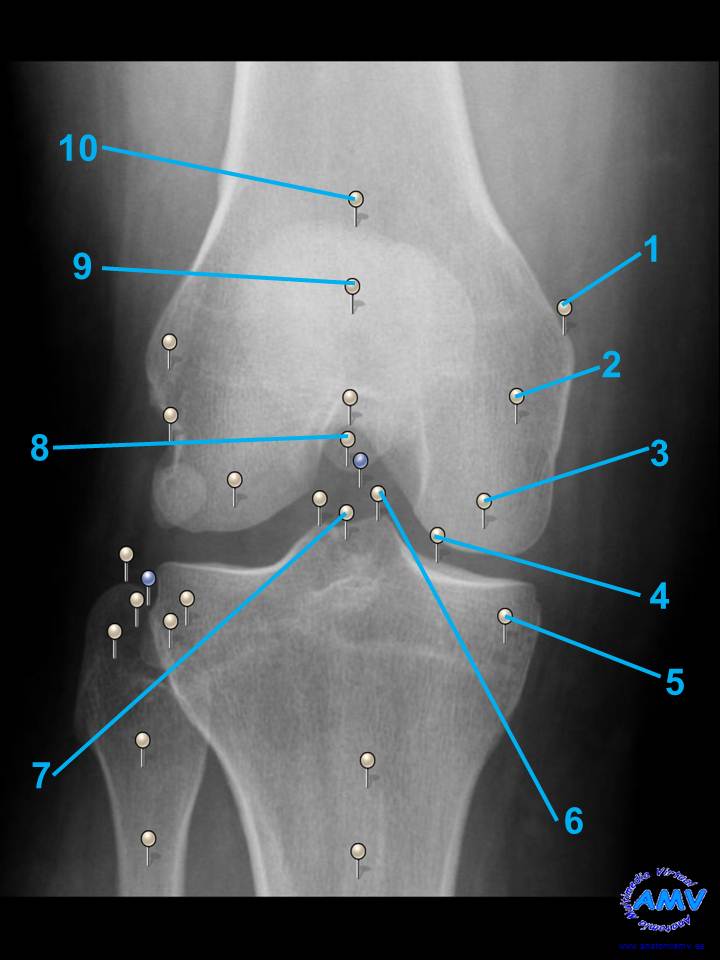

rx_mi_06.jpgIndique que estructura se señala con el número correspondiente:

El nº 1 señala .

El nº 2 señala .

El nº 3 señala .

El nº 4 señala .

El nº 5 señala .

El nº 6 señala .

El nº 7 señala .

El nº 8 señala .

El nº 9 señala .

El nº 10 señala .